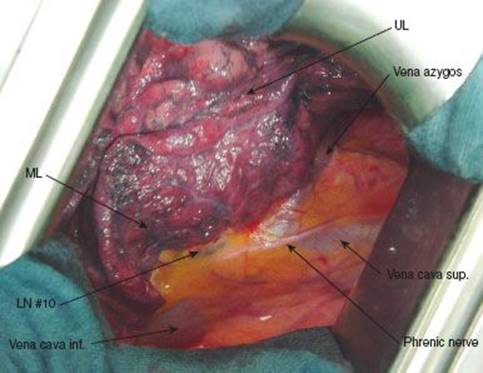

Dissection starts at the anterior hilum by incision of the mediastinal pleura. To do so, the lung is pushed dorsally and held in this position either with a sponge stick or a parenchymal clamp (i.e., Duval lung forceps). This maneuvre exposes the anterior hilum with the vessels, fatty tissue, lymph nodes (station 10), and phrenic nerve. Care has to be taken to prevent harm to the phrenic nerve which lies close to the hilar vessels and may be buried in fatty tissue. There are always small vessels accompanying the nerve longitudinally which are better visible than the nerve itself (Fig. 11.1). The pleura overlying the pulmonary vessels is grasped with DeBakey forceps and incised perpendicular to the axis of the vein with electrocautery or Metzenbaum scissors (Fig. 11.2). Preparation of vessels is performed until the vessel wall is bare. The upper pulmonary vein is the first vessel encountered as it partially overlaps the mainstem of the pulmonary artery (Fig. 11.3).

Figure 11.1 Situs with anterior hilum: Mediastinal pleura overlying the vascular structures. Phrenic nerve, vena cava, and azygos vein clearly visible.